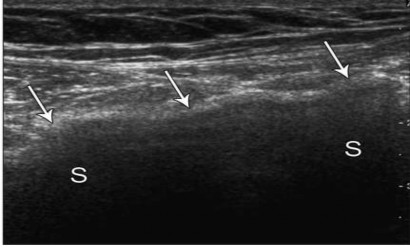

Tiến hành siêu âm sau 1 năm nhằm: khảo sát, đánh giá mô xơ tạo thành sau đặt tấm lưới nhân tạo polypropylene ở vùng bẹn, dựa vào nguyên lý: vùng phía trước tấm lưới xuất hiện đường tăng âm, phía sau tấm lưới là dải bóng đen.

Hình 2.11. Tấm lưới đặt ở vùng bẹn phải, siêu âm xuất hiện tấm lưới tăng âm (hình mũi tên) với đường lượn sóng và dải bóng đen ở phía sau (S). Nguồn: Jamadar D. A., Jacobson J. A., (2008) [74].